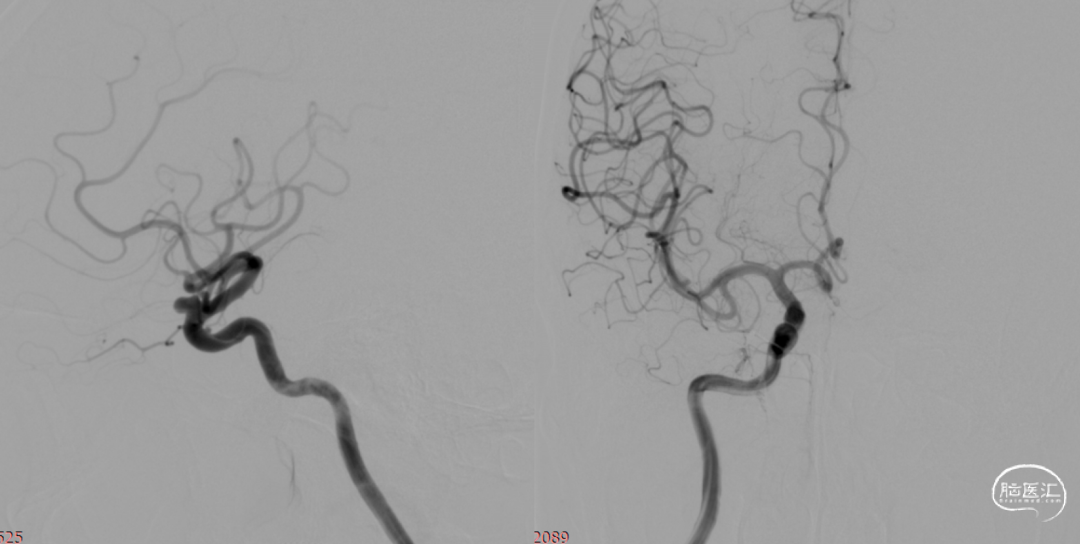

疏松填塞弹簧圈后正侧位造影。

术后即刻。

术后即刻,可见动脉瘤瘤腔内血液滞留明显。

术后即刻,正侧位造影。